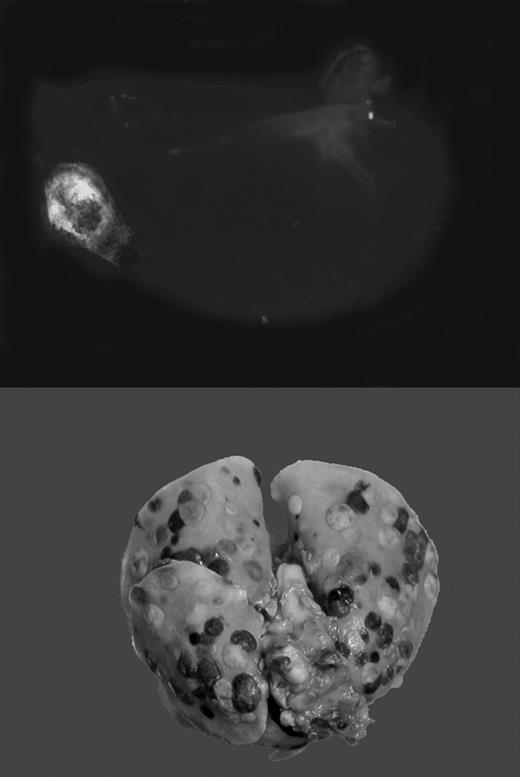

Gαq deficiency dramatically diminishes the metastatic potential of circulating tumor cells. See the complete figure in the article beginning on page 178.

The current article by Palumbo and colleagues follows an earlier lead suggesting that platelet aggregation around procoagulant tumor cells shields these cells from attack by cytolytic natural killer (NK) cells.4 NK cells eliminate the vast majority of circulating tumor cells, and NK cell elimination or inhibition results in greatly exaggerated metastasis. NK cell–mediated tumor killing requires direct contact with the target cell, possibly via transcellular interleukin 15 presentation.5 The acquisition of a platelet cloak around the tumor cell could in theory prevent such interactions, and allow the tumor cell to escape the surveillance by cells of the innate immune system. Palumbo et al test this hypothesis by employing fibrinogen-deficient mice, mice with aggregation-defective platelets (lacking the signal transducer Gαq), and mice with defective NK cell function. They demonstrate that the metastasis-enhancing effect of fibrinogen and platelets is completely abolished in the absence of NK cells, thus providing an independent and convincing experimental verification of the hypothesis proposed by Nieswandt and colleagues.4 It remains to be shown whether platelets protect tumor cells indeed simply by providing a physical barrier, or whether platelets modulate NK function in some additional way. The current article by Palumbo et al also establishes an experimental paradigm in which NK-independent mechanisms linking tumor metastasis and hemostasis can be addressed. Insight into the role of platelets in the adhesion of tumor cells to endothelium, the effects of thrombin on mobilization of tumor cells, and the role of coagulation, platelets, and receptors in the extravasation/diapedesis of tumor cells is sure to emerge from further analysis of these pathways in NK-deficient mice.